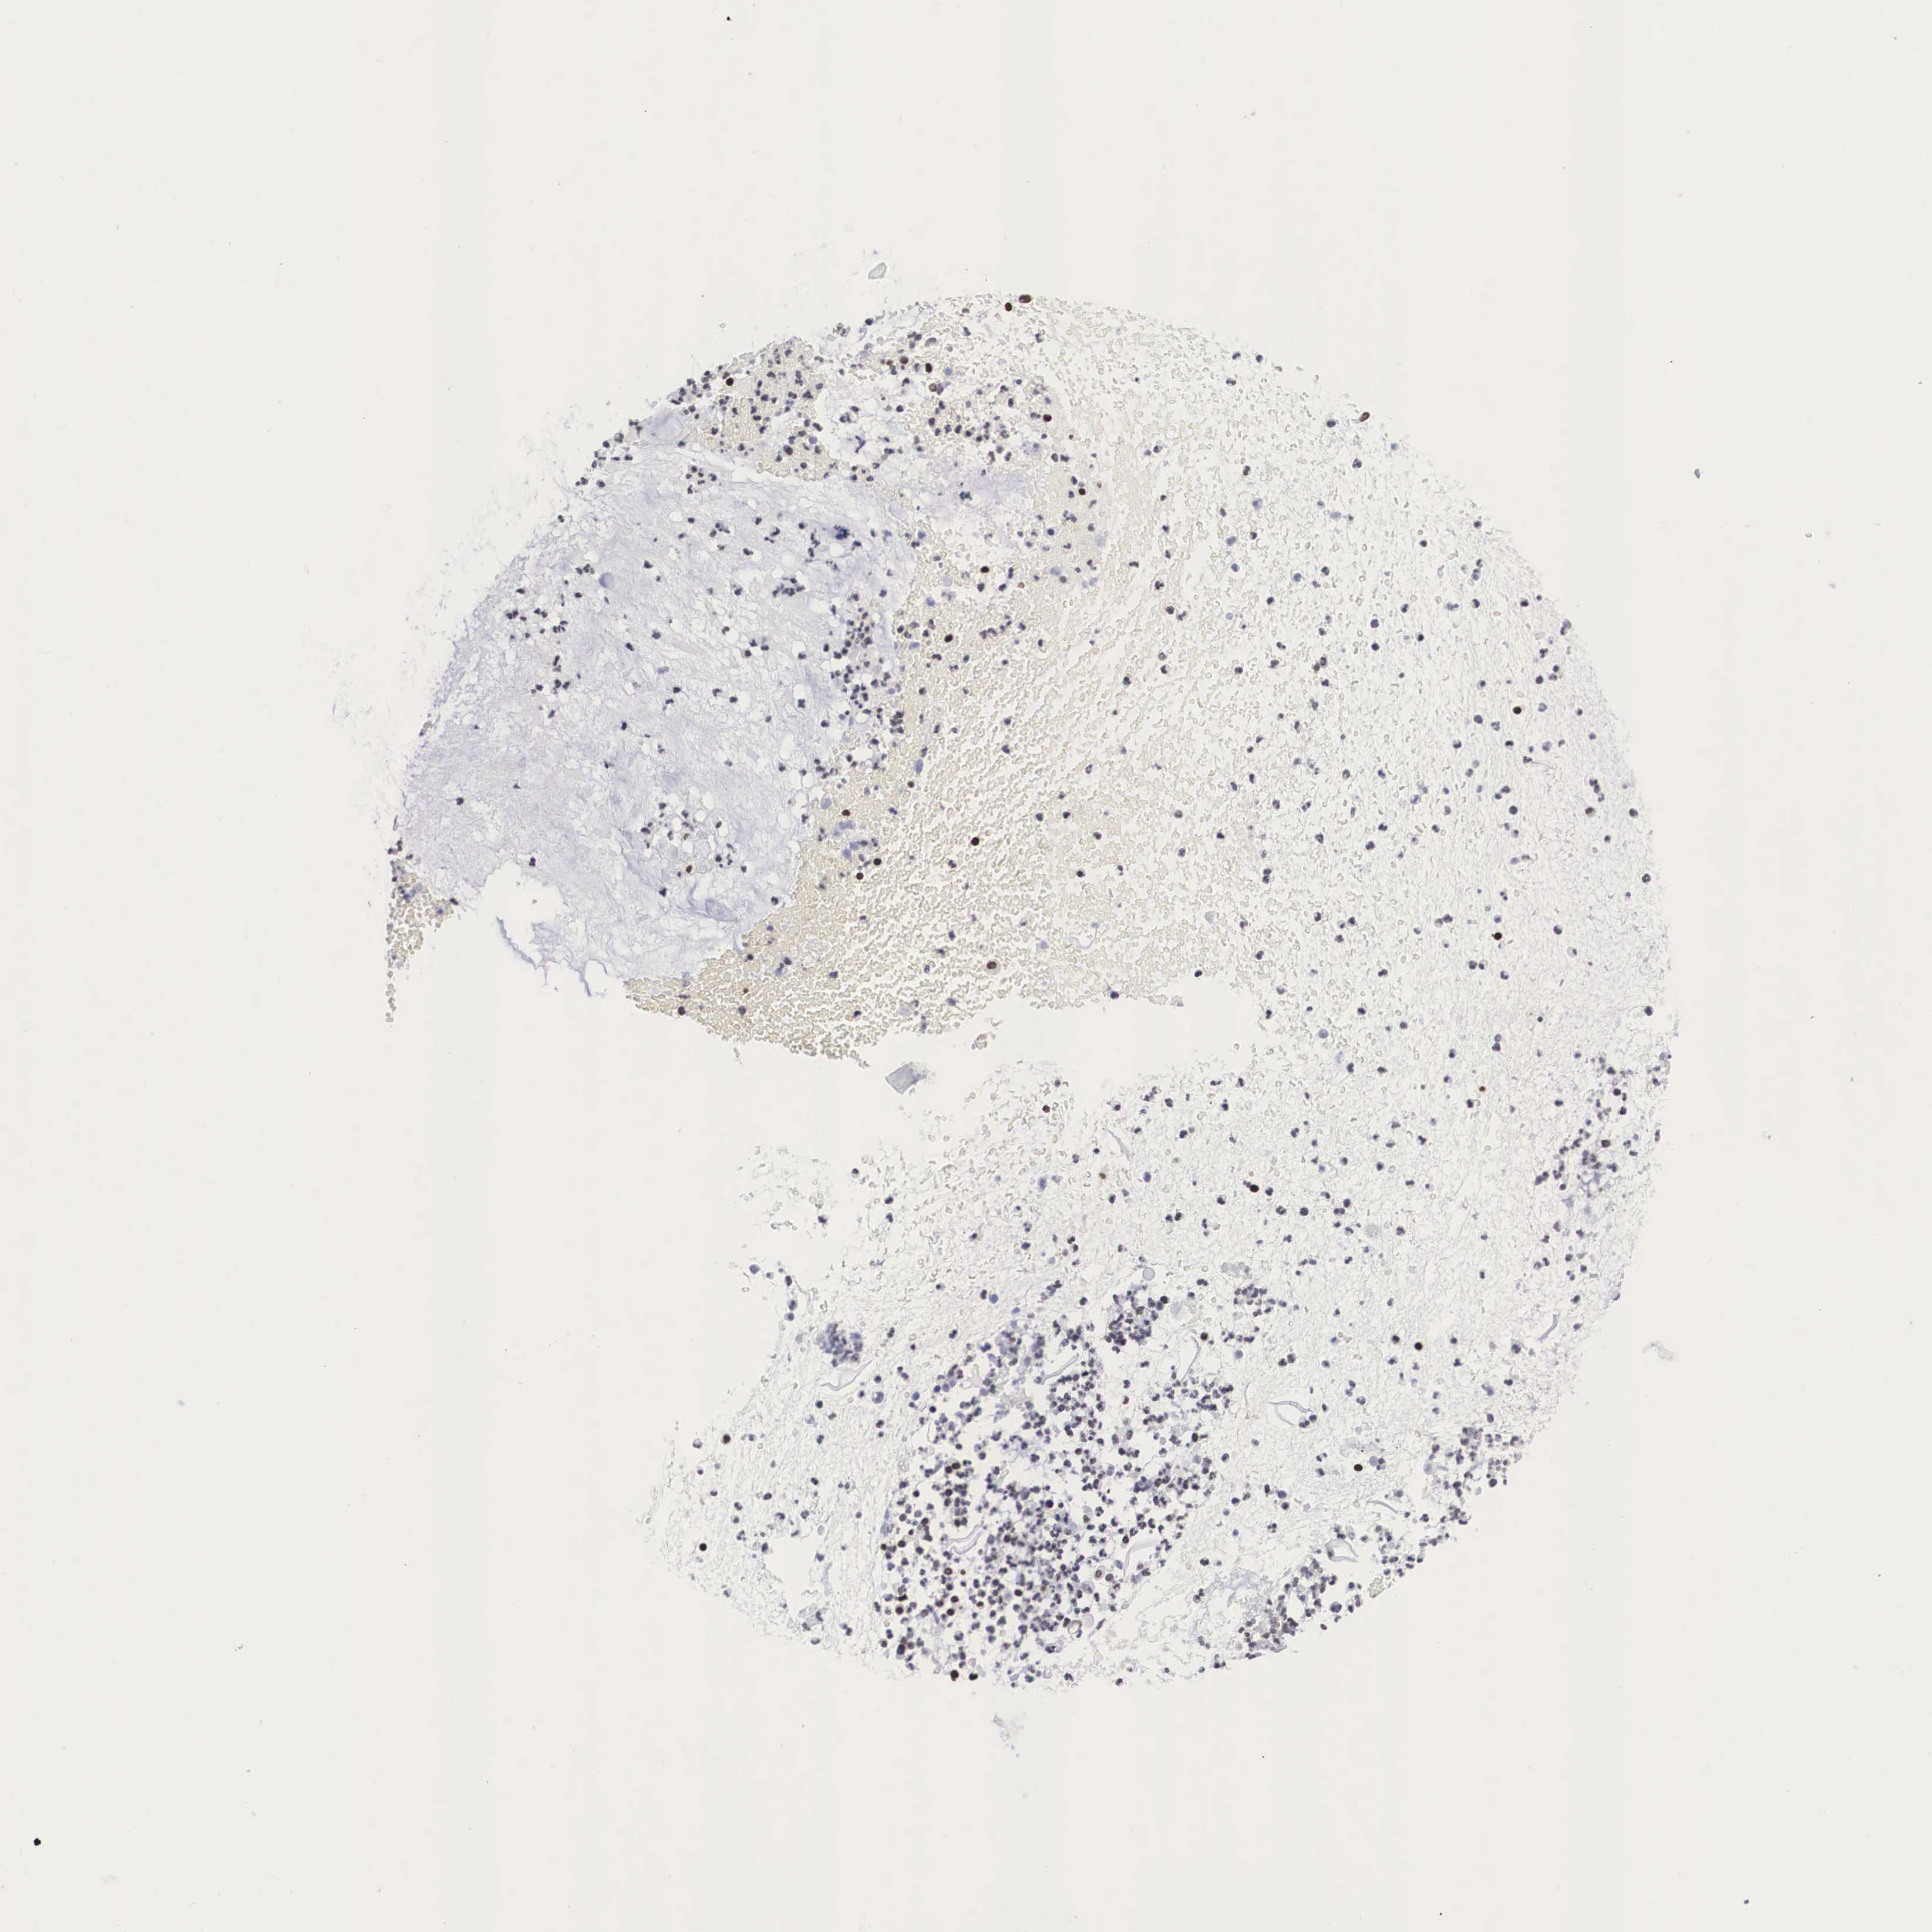

CERVICAL CANCER - Protein expressioni

A mouse-over function shows sample information and annotation data. Click on an image to view it in a full screen mode. Samples can be filtered based on level of antibody staining by selecting one or several of the following categories: high, medium, low and not detected. The assay and annotation is described here.

Note that samples used for immunohistochemistry by the Human Protein Atlas do not correspond to samples in the TCGA dataset.

Antibody stainingi

Antibody staining in the annotated cell types in the current human tissue is reported as not detected, low, medium, or high, based on conventional immunohistochemistry profiling in selected tissues. This score is based on the combination of the staining intensity and fraction of stained cells.

Each image is clickable and will lead to virtual microscopy that enables deeper exploration of all samples and also displays staining intensity scores, fraction scores and subcellular localization as well as patient and tissue information for each sample.

Antibody HPA000593

Antibody HPA001341

Antibody CAB037264

Staining

High

Medium

Low

Not detected

Intensity

Strong

Moderate

Weak

Negative

Quantity

>75%

75%-25%

<25%

None

Location

Nuclear

Cytoplasmic/membranous

Cytoplasmic/membranous,nuclear

Adenocarcinoma, NOS

Squamous cell carcinoma, NOS